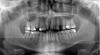

wind Опубликовано 22 апреля, 2010 Поделиться Опубликовано 22 апреля, 2010 (изменено) Добрый день мне 38 лет и захотелось навести порядок во рту те1 Поставить импланты на место отсутствуюших 4-к( отсутствует с 28 лет)2 раздвинуть зубы3 поставить имплант на место резца (отсутствует с 12 лет)Там где я живу не сильно большой выбор кому "отдаться" и самое главное поговорив с несколькими ортодонтами , меня зачаровало различие в подходах и оценки ситуации:1 оценки срока на раздвижение зубов розняться от 1,5 года до 3лет- ну это ладно , понять можно2 было мнение ,что есть небольшой шанс( но все же есть), когда они просто не раздвинутся , останутся на месте и все - возможно ли такое?3 кто говорит, что брекеты достаточно будет поставить только на верхнюю челюсть, а кто ,что на обе - и это обязательно- кто из них прав?( разумная экономия средств приветствуется)4 кто говорит, что импланты на 4-и нужно ставить после того как процесс раздвижения зубов закончится по тому что в противном случае: 1.1 импланты вылетят -1я версия 1.2 не дадут раздвинуться зубам-2я версияа кто говорит ставь ничего страшного, не помешает, и проблем не будет -3я версия5 и последнее - кто то говорит, лучше ничего не двигай вообще- типа опасно ,сложнореализуемо и тп.помогите разобраться пожалуйста Всем заранее благодарен....PS хочу добавить,1 перфекционизмом не страдаю , поэтому готов обойтись улыбкой по проще чем у звезды голивуда, меня устроит отсутствие щели спереди 2 не хотелось бы попасть в грусную ситуацию о которой пишут некоторые здесь люди(про некачественные услуги и потерянное зря время) Изменено 22 апреля, 2010 пользователем wind Ссылка на комментарий

Премоляр Опубликовано 22 апреля, 2010 Поделиться Опубликовано 22 апреля, 2010 Судя по вашей инфе,можно предложить-1-брекет система на 2 челюсти2-удаление корня 5ки сверху справа3-закрытие промежутка слева сверху дистализацией 4.3.24-импланты в обл резца и 4 слева...наверно есть еще варианты Ссылка на комментарий